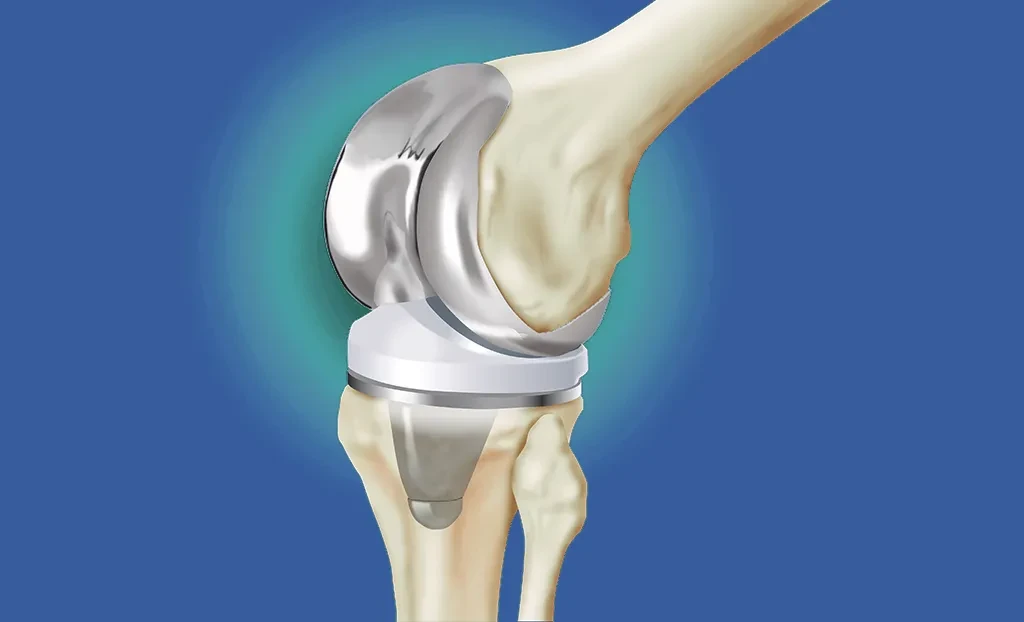

Якщо порівнювати наше тіло з автомобілем, коліно — це амортизатор і підшипник водночас. Воно поглинає удари при кожному кроці, забезпечує плавність рухів, витримує вагу всього тіла. Усередині цього суглоба — ціла система з кісток, хрящів, зв’язок і менісків, які працюють синхронно.

Та саме через таку складність коліно стає вразливим. Різкий поворот на футбольному полі — і ось уже розрив зв’язок. Падіння на слизькій дорозі — ушкодження меніска. Роки важкої фізичної роботи — артроз, що поступово руйнує хрящ. А для когось це можуть бути наслідки серйозних травм у зоні бойових дій, де реабілітація після поранення стає довгим шляхом до повернення навіть базової рухливості.

Коліно поєднує складну будову з величезними щоденними навантаженнями. Воно має кістки, хрящі, зв’язки та меніски, які працюють синхронно під час кожного кроку. Травмуються через спортивні ушкодження, падіння, артрозні зміни або серйозні поранення. Саме ця комбінація робить коліно особливо вразливим.